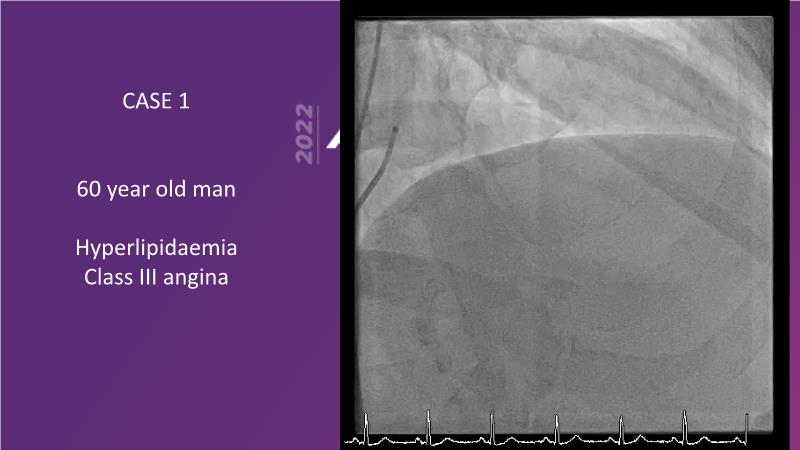

With this session, keep up to date on the evidence, trials and outcome data for intravascular lithotripsy in severely calcified lesions. Learn how to use this technique in real-world patients and understand its role in the treatment algorithm for severely calcified coronary lesions.

- To learn how to use intravascular lithotripsy in real-world patients with severely calcified coronary lesions